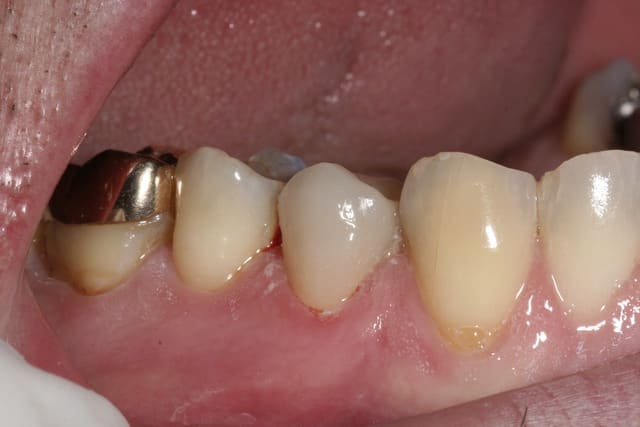

Img 3997 dk8k6g - Eugenol

Img 0426 jmyxaz - Eugenol

Img 5364 apxucc - Eugenol

mg 7102 nax8qq - Eugenol

mg 6276 umegd9 - Eugenol

mg 6424 aeia7y - Eugenol

mg 7430 nqcynh - Eugenol